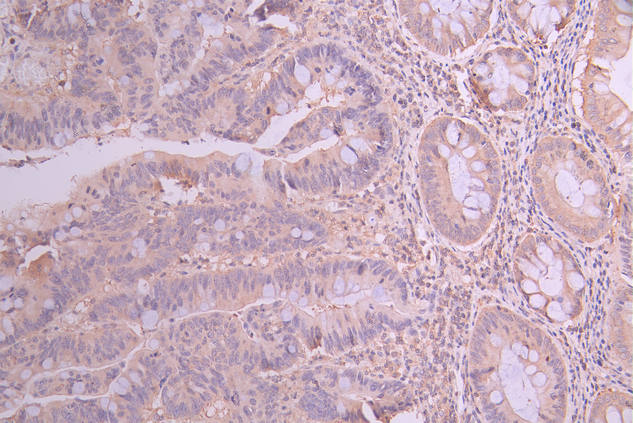

IHC image of CSB-RA295233A0HU diluted at 1:100 and staining in paraffin-embedded human colorectal cancer performed on a Leica BondTM system. After dewaxing and hydration, antigen retrieval was mediated by high pressure in a citrate buffer (pH 6.0). Section was blocked with 10% normal goat serum 30min at RT. Then primary antibody (1% BSA) was incubated at 4°C overnight. The primary is detected by a Goat anti-rabbit polymer IgG labeled by HRP and visualized using 0.05% DAB.